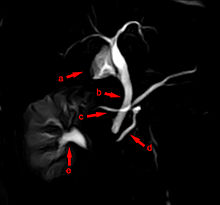

Der etwa zwei Millimeter weite Ausführungsgang der Bauchspeicheldrüse (Ductus pancreaticus, Wirsung-Gang) mündet gemeinsam mit dem Hauptgallengang (Ductus choledochus) oder nahe diesem in den Zwölffingerdarm. Diese Mündung stellt eine warzenförmige Erhebung dar (Papilla duodeni major oder VaterschePapille). Bei manchen Individuen ist ein zweiter, kleiner Ausführungsgang vorhanden, der Ductus pancreaticus accessorius (Santorini-Gang), der dann auf der kleinen Zwölffingerdarmwarze (Papilla duodeni minor) in den Zwölffingerdarm mündet.[2]